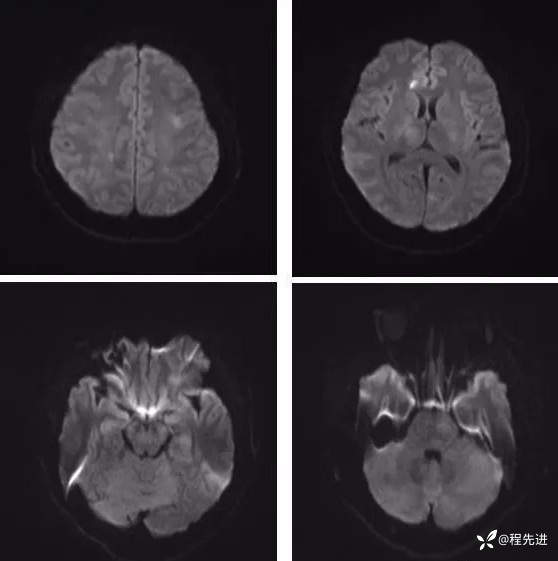

【神经】特别精彩病例|发热、头痛20天

病史:患者20天前无明显诱因下出现畏寒、发热,热峰39.5℃,热型不规则,不伴咽痛,流涕,感头昏,有头痛,阵发性加剧,伴呕吐,为胃内容物非喷射性。患者在外院查头颅CT示:未提示异常。外院予以“头孢类、退热药”,无明显好转。我院急诊予以“泼尼松,热毒宁"治疗无明显好转

外院胸部CT:两肺弥漫分布结节斑片影,考虑感染